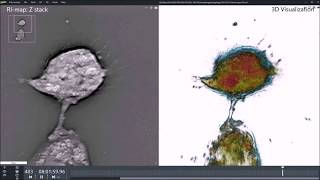

9.2 Basal autophagy in single MCF7 cells (real time) video

9.2 Basal autophagy in single MCF7 cells (real-time)

Microinjection Dextran Red and GFP mRNA into MCF7 cells on Etaluma LS720 by Zambon Lab at KGI Glioblastoma cells undergoing autophagy observed with holo-tomographic microscope

Glioblastoma cells undergoing autophagy observed with holo-tomographic microscope Minimum fasting length required for autophagy | Guido Kroemer